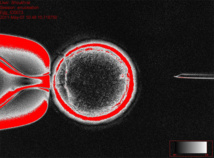

Este sistema consiste en trasplantar el núcleo de una célula –que contiene el material genético o ADN de un individuo, en un ovocito (un óvulo inmaduro) al que previamente se le ha sustraído su propio material genético.

Se considera que el ovocito tiene la capacidad de reprogramar el programa de expresión génica celular, reiniciándolo de alguna manera, de forma que la célula nueva resultante sea capaz de dar lugar a cualquier otro tipo de célula. En otras palabras: el óvulo fertilizado se desarrolla y finalmente produce células madre.

Este sistema consiste en trasplantar el núcleo de una célula –que contiene el material genético o ADN de un individuo, en un ovocito (un óvulo inmaduro) al que previamente se le ha sustraído su propio material genético.

Se considera que el ovocito tiene la capacidad de reprogramar el programa de expresión génica celular, reiniciándolo de alguna manera, de forma que la célula nueva resultante sea capaz de dar lugar a cualquier otro tipo de célula. En otras palabras: el óvulo fertilizado se desarrolla y finalmente produce células madre.

La clave de este éxito fue encontrar la manera de estimular los óvulos para mantenerlos en un estado llamado "metafase", durante la transferencia nuclear. La metafase es una etapa del proceso de división natural de la célula (o meiosis) en la que el material genético se alinea en la línea media del huso (conjunto de microtúbulos en el núcleo celular), antes de que la célula se divida.

El equipo de investigación descubrió que mantener químicamente la metafase durante todo el proceso de transferencia nuclear impide que el proceso se estanque, y permite que las células se desarrollen y produzcan células madre.

La clave de este éxito fue encontrar la manera de estimular los óvulos para mantenerlos en un estado llamado "metafase", durante la transferencia nuclear. La metafase es una etapa del proceso de división natural de la célula (o meiosis) en la que el material genético se alinea en la línea media del huso (conjunto de microtúbulos en el núcleo celular), antes de que la célula se divida.

El equipo de investigación descubrió que mantener químicamente la metafase durante todo el proceso de transferencia nuclear impide que el proceso se estanque, y permite que las células se desarrollen y produzcan células madre.

Ovocito conteniendo el núcleo de la célula de piel. Imagen: Cell. Fuente: OHSU.